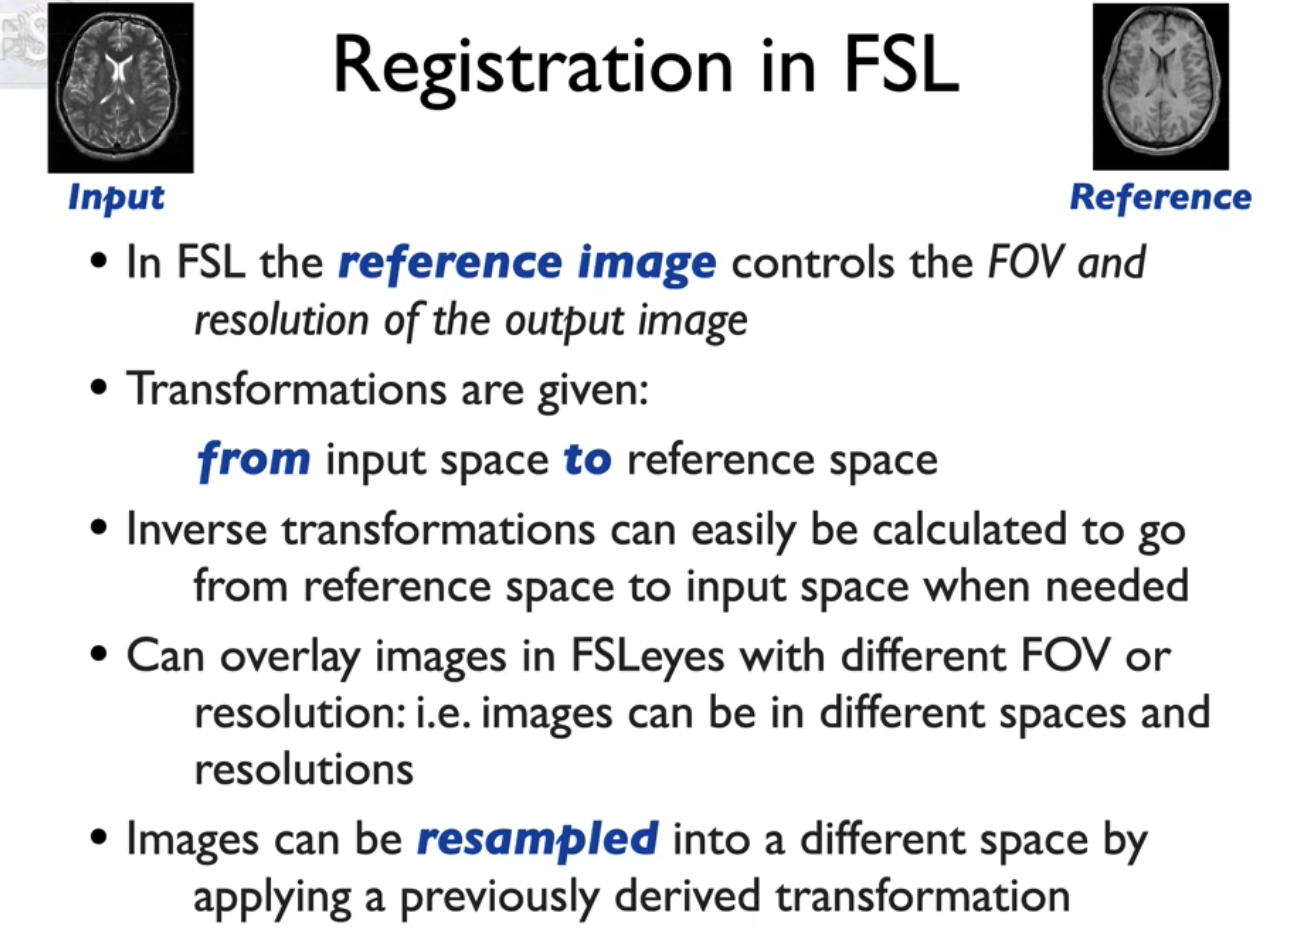

我们要使这两个序列的图像对齐,有两种方法。一个是把T2w配到T1w上(T1w作为参考图像,T2w作为输入图像);另一种就是反过来,T1w配到T2w.

一般原则是,把分辨率好的,对比度好的作为参考图像。

我们这种从图像直接配准到参考空间,只需要一步配准,因此可以叫 single_stage registration(单阶段配准)。

对此,还有多阶段配准。

功能成像或扩散成像,然后我们也有一个特定的t1加权结构扫描主题,我们还需要将东西放入标准空间,因此我们现在有三个不同的空间,我们将进行多阶段配准,既可以在我们想要的任何空间组合之间移动,也可以让我们更好地配准

如图,我们先把epi功能像配到同一个病人的T1w上,只需要用自由度为6,线性配准进行,再把T1W配到标准空间。这时由于是不同个体,解剖差异较大,使用自由度12,非线性配准(FNIRT)